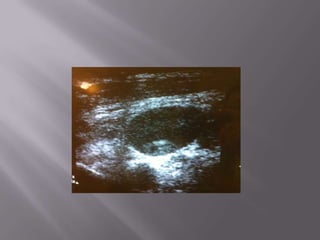

EVIDÊNCIA ROBUSTA -> Menos complicações, menos tentativas, menor tempo para o procedimento  Só é possível saber o paciente difícil de puncionar após tentativa frustrada  Tentativas frustradas chegam a 14-20% no acesso jugular e 15-40% no acesso femural.  Permite escolher a melhor veia para punção ( ÓBVIO!!!!!!!!!!!!)